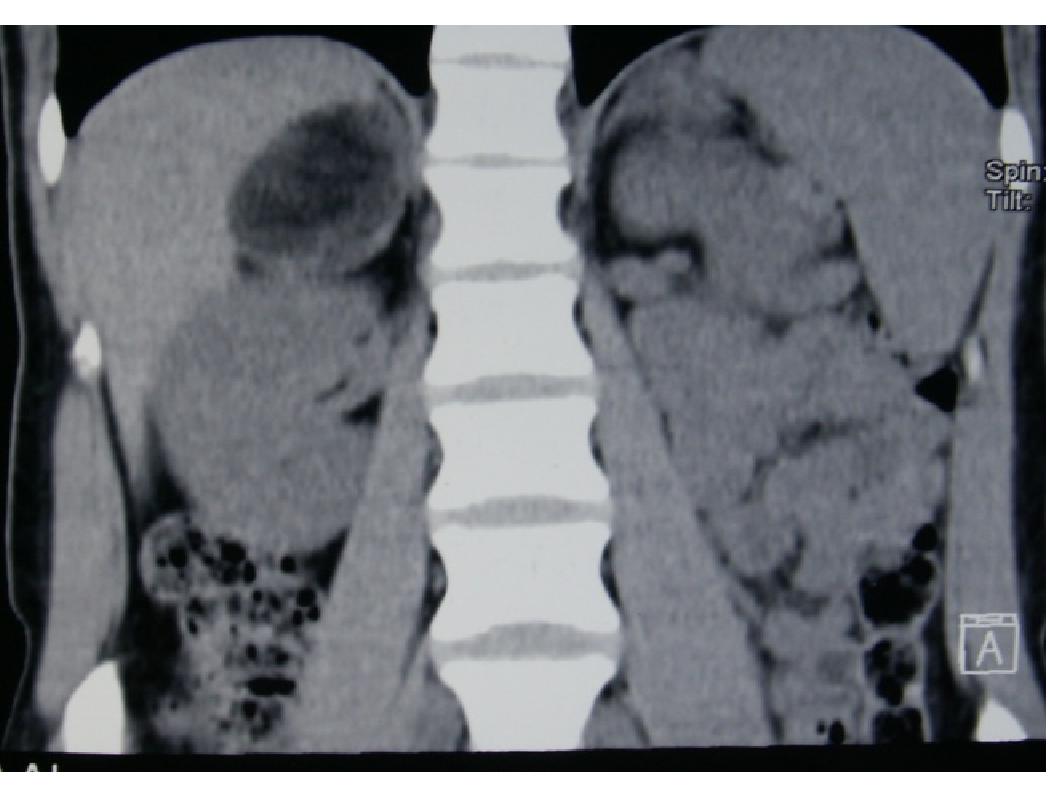

Source: Cancer Urology; Том 13, № 2 (2017); 121-123 ; Онкоурология; Том 13, № 2 (2017); 121-123 ; 1996-1812 ; 1726-9776 ; 10.17650/1726-9776-2017-13-2

Subject Terms: лапароскопическая адреналэктомия, adrenal myelolipoma, laparoscopic adrenalectomy, миелолипома надпочечника

Relation: https://oncourology.abvpress.ru/oncur/article/view/654/667; https://oncourology.abvpress.ru/oncur/article/downloadSuppFile/654/442; https://oncourology.abvpress.ru/oncur/article/downloadSuppFile/654/443; https://oncourology.abvpress.ru/oncur/article/downloadSuppFile/654/444; https://oncourology.abvpress.ru/oncur/article/downloadSuppFile/654/445; https://oncourology.abvpress.ru/oncur/article/downloadSuppFile/654/446; Dan D., Bahadursingh S., Harinaran S. et al. Extra-adrenal perirenal myelolipoma. A case report and review literature. G Chir 2012;33(3);62–5. DOI:10.11138/2012.33.5.62-5. PMID: 22525547.; Sanders R., Bissada N., Curry N., Gordon B. Clinical spectrum of adrenal myelolipoma: analysis of 8 tumors in 7 patients. J Urol 1995;153(6):1791–3. DOI:10.4103/0970-1591.152807. PMID: 7752318.; Han M., Burnett A.L., Fishman E.K., Marshall F.F. The natural history and treatment of adrenal myelolipoma. J Urol 1997;157(4):1213–6. PMID: 9120904.; Bhansali A., Dash R.J., Singh S.K. et al. Adrenal myelolipoma: profile of six patients with a brief review of literature. Int J Endocrinol Metab 2003;1:33–40.; Clark O.H., Duh Q.Y., Perriet N.D., Jahan T.M. Endocrine tumors. Atlas of Clinical Oncology. BC Decker, 2003.; Бондаренко В.О., Дэпюи Т.И., Бондаренко Е.В. и др. Миелолипома надпочечников. Эндокринная хирургия 2013;(4):25–38. [Bondarenko V.O., Depyui T.I., Bondarenko E.V. et al. Adrenal myelolipoma. Endokrinnaya khirurgiya = Endocrine Surgery 2013;(4):25–38. (In Russ.)]. DOI:10.14341/serg2013425-38.; Lin P., Yang F. Bilateral giant adrenal myelolipomas: a case report and literature review. Chin J Radiol 2008;33:261–4.; Wrightson W.R., Hahm T.X., Hutchinson J.R., Cheadle W. Bilateral giant adrenal myelolipomas: a case report. Am Surg 2002;68(6):588–9. DOI:10.1159/000078383. PMID: 12079144.; Fernandes G.C., Gupta R.K., Kandalkar B.M. Giant adrenal myelolipoma. Indian J Pathol Microbiol 2010;53(2):325–6. DOI:10.4103/0377-4929.64314. PMID: 20551546.; Chung H., Luo F., Wu T., Tsai Y. Adrenal myelolipoma with spontaneous hemorrhage. Urol Sci 2010;21(3):152–4.; Chakrabati I., Ghosh N., Das V. Giant adrenal myelolipoma with hemorrhage masquerading as retroperitoneal sarcoma. J Midlife Health 2012;3(1):42–4. DOI:10.4103/0976-7800.98818. PMID: 22923980.; Gerson G., Bêco M. Giant retroperitoneal myelolipoma: case report and literature review. J Bras Patol Med Lab 2015:48–51. DOI:10.5935/1676-2444.20150010.; Al Hatthi B., Riaz M.M., Al Khalaf A.H. et al. Adrenal myelolipoma a rare benign tumour managed laparoscopically: report of two cases. J Minim Access Surg 2009;5(4):118–20. DOI:10.4103/0972-9941.59312. PMID: 20407573.; https://oncourology.abvpress.ru/oncur/article/view/654